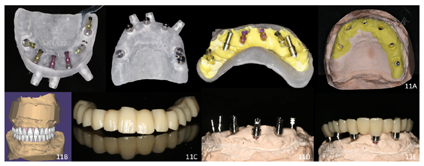

治疗过程:(1)术前准备:①藻酸盐取初印模,制作个性化托盘(图4);②用个性化托盘取硅橡胶终印模,灌制终模型;③制作光固化树脂

托及蜡堤(图5),面部比例二等分法确定垂直距离,肌肉疲劳法及吞咽咬合法确定水平关系,面弓转移患者颌位关系,上

架;④排牙,制作放射导板(图6A);⑤试戴放射导板(图6B~D),拍摄两次CBCT(患者佩戴放射导板拍摄CBCT以及放射导板单独拍摄CBCT)。(2)方案设计:①将两次CBCT获取的DICOM数据导入种植设计软件重叠(图7),以修复为导向指导上下颌种植体位置摆放(图8、图9);②生成并打印手术导板(图10)。(3)利用手术导板和导板锁,翻制模型,制作临时修复体(图11)。(4)一期手术过程:铺巾消毒,局麻后拔除上下颌余留牙,搔刮拔牙窝内炎性肉芽组织,于34-36、44-46区牙槽嵴顶近远中向切开牙龈,翻瓣。就位并固定手术导板,于11、13、16、22、25、26、32、34、36、42、44、46定点,按术前设计方案植入NobelParallelTM ConicalConnection种植体。除26区种植体外,其余种植体初期稳定性均达到35N.cm以上,就位复合基台,戴入保护帽,修整牙龈黏膜,缝合牙龈(图12A~F)。术后拍摄全景片(图13)。次日复诊,取下保护帽,戴入预制的临时修复体,调合(图12G)。

治疗结果:术后3个月全景片显示种植体骨结合良好(图14)。26牙行二期手术,就位复合基台,戴入保护帽。两周后,取下临时修复体,制取上下颌硅橡胶印模,利用临时修复体交叉上

架转移患者颌位关系。设计数字化桥架(图15),切削铝制支架。试戴铝制支架,拍摄全景片显示支架被动就位良好(图16)。按照铝制支架切削纯钛支架,上聚合瓷,患者右侧咬合空间不足,设计金属

面。戴入最终修复体,调合(图17)。种植修复前后面像对比,患者面下1/3高度恢复良好(图18)。